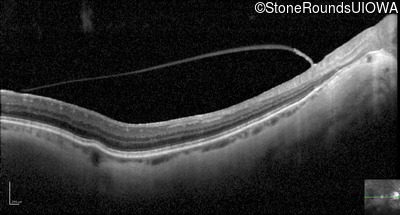

Optical Coherence Tomography - Left - 20/40 +2

Exemplar / OCT Stack

OCT Stack